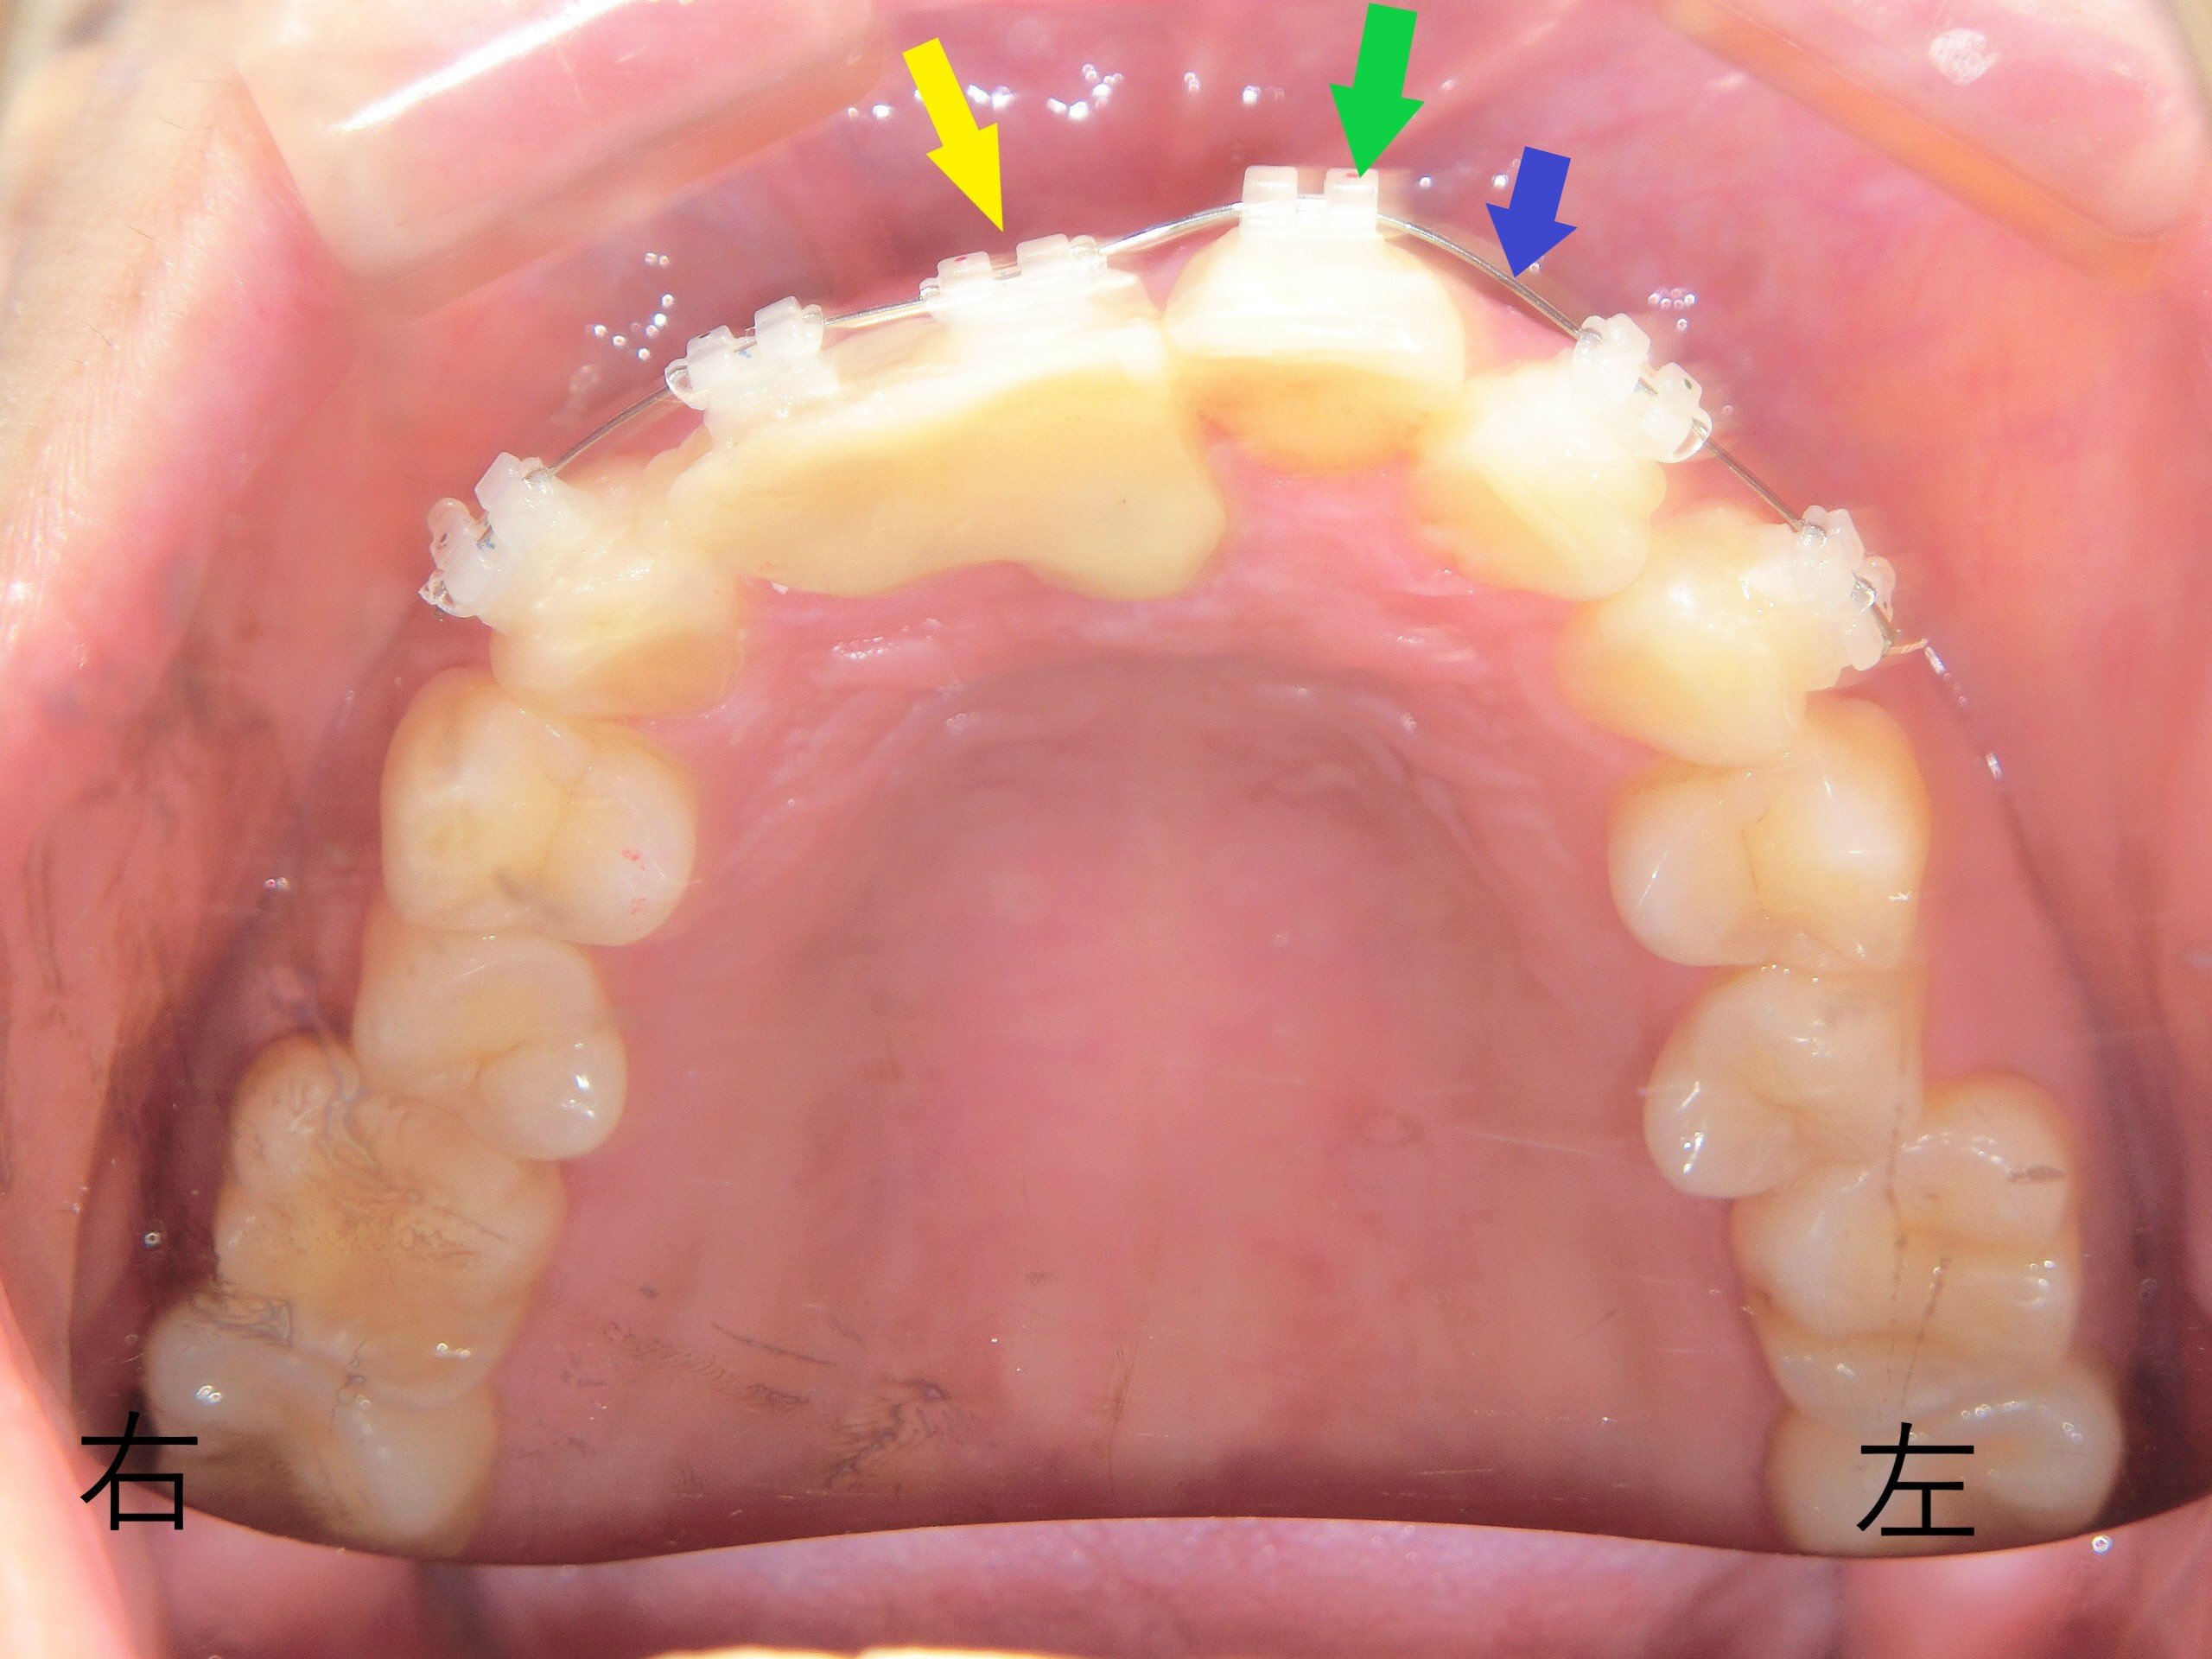

レントゲン写真からは、仮歯の下に2本の過剰歯(青色矢印)が確認されました。

患者様は右上前歯にインプラント治療を希望されたため、仮歯下の1本の過剰歯(青色矢印)を抜歯しました。もう1本の過剰歯(赤色矢印)は、位置的に支障がないため経過観察としました。

前歯部のCT画像で、左上前歯(緑色矢印)を内側に移動させる計画を立てました。通常、プチ矯正では前歯を内側に引っ込める治療は難しく、アライナー矯正やワイヤーによる全顎矯正が適応範囲です。

本症例では、右上前歯をインプラントで固定したことで、強固な固定源を得られたため、左上前歯を内側に動かすことが可能となりました。